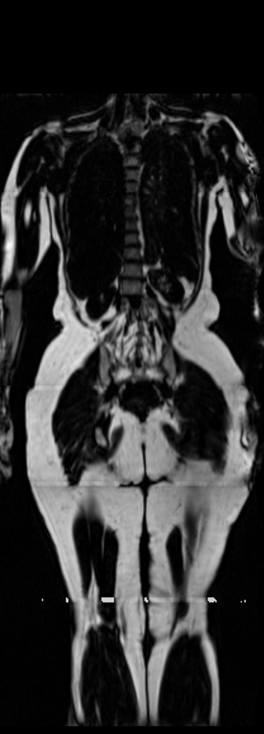

Notably, X-Diffusion achieves state-of-the-art dB for a few input slices while baselines require more than 60 input slices to achieve similar performance (Figure 7). The margin is more than 12 dB PSNR for the 1-slice input in both the BRATS and the UK Biobank benchmarks (see Table 1 and Figure 6). For reference, two randomly sampled MRIs from UK Biobank would have a PSNR of 15.95 dB 0.36 (on 4800 randomly sampled examples). Omitting the preprocessing step of alignment DXA to MRI, leads to a drop of PSNR on average by 2.87 dB (29.01 dB 26.14 dB). The slices from 3D reconstructed volumes at varying depths and axis of rotation, visually match the ground truths for both brain and whole-body scans (see Figures 4 and 5 left). We also plot the error map (Figure 3) and the spread of the error (Figure 5 right) of such X-Diffusion generations to highlight the differences with the ground truth MRIs.

Preservation of Spine Curvature. For the spine segmentation on UK Biobank, we use a UNet++ model [83] with Dice Loss. We use a model trained to predict curves on DXA on UK Biobank [11]). We measure the Pearson correlation factor [11] of spine curvature measured on the generated MRIs where the input is a single MRI coronal slice, a single sagittal slice, or from the paired DXA, against the curvature of reference real MRIs of the same samples. The correlation coefficients are 0.89 for the coronal MRIs, 0.88 for the sagittal MRIs, and 0.87 for the DXAs on the test set of 308 human-annotated angles. We can then bin the curvature of the spines under different scoliosis categories based on human-annotated angles: mild: , moderate: , and severe . We show the results in Figure 8. This illustrates that the generated MRIs preserve the spine curvature from normal to severe scoliosis cases. Additional details about spine curvature are provided in supplementary material.